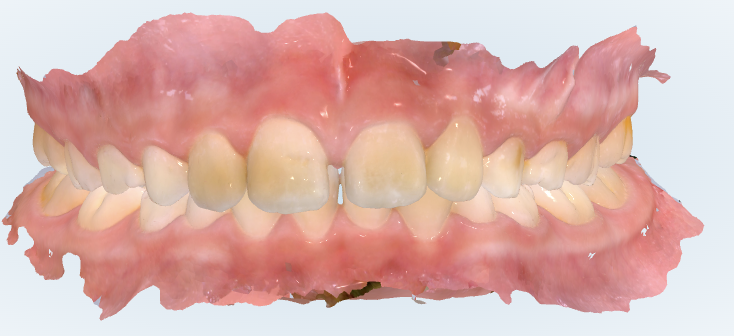

初診時の画像診断

前歯の咬み合わせが深いため、下の前歯があまり見えません。

ガタガタは少ないです。